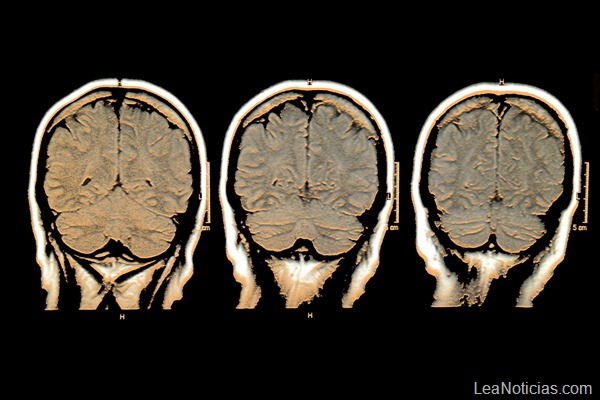

El coma se indujo con un anestésico, el isoflurano, y fue profundo pero completamente reversible. Los gatos pasaron de esta manera la línea plana del electroencefalograma, un límite que está asociado con el silencio de la corteza cerebral, una región formada por un manto de tejido nervioso que cubre la superficie de los hemisferios cerebrales y que rige el funcionamiento de todo el cerebro. En ella ocurren además la percepción, la imaginación, el pensamiento, el juicio y la decisión.

Estas oscilaciones, hasta ahora desconocidas, eran transmitidas a la parte principal del cerebro, la corteza. Los científicos han concluido que las ondas Nu-complexes observadas en los gatos eran las mismas que las detectadas en el paciente humano.

Esta «muerte parcial» del cerebro se debería a que el proceso de muerte cerebral sigue un orden temporal: en primer lugar dejan de funcionar “las estructuras más modernas filogenéticamente y más complejas, como la corteza”. Después, se detienen “otras estructuras más antiguas, como el hipocampo, que pertenece al sistema límbico o cerebro emocional”, explica Rubia.